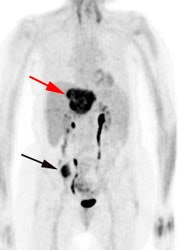

Initial staging for colorectal carcinoma: The patient below presented for evaluation of colorectal carcinoma. The CT scan demonstrated a large liver mass (red arrows) compatible with metastatic disease. The patient's cecal mass (black arrow on PET scan) was not detected on the CT study (white arrow). No other lesions were identified on the PET scan. |